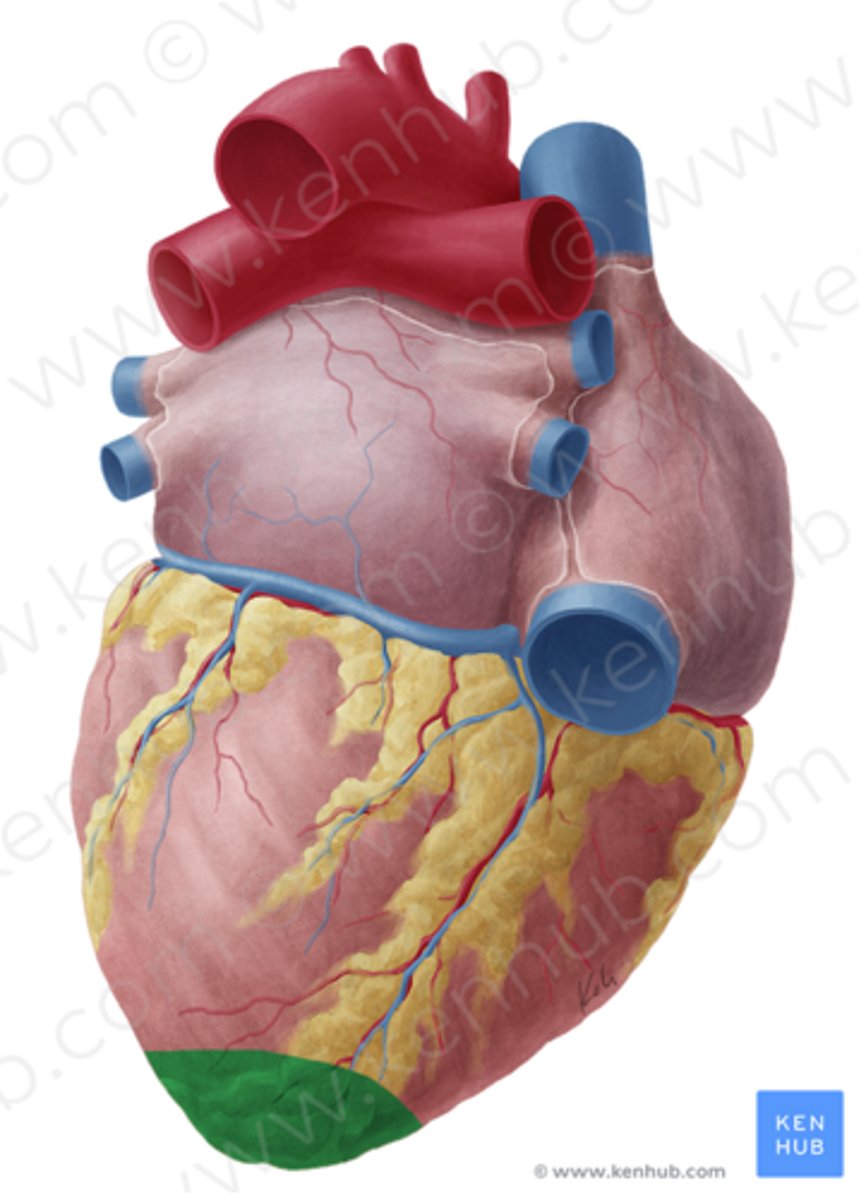

Jakie powierzchnie wyróżniamy w sercu?

-przednia - mostkowo-żebrowa

-dolna - przeponowa

-płucna lewa

-płucna prawa

Co rozdziela przedsionki od komór na powierzchni serca?

bruzda wieńcowa

bruzda wieńcowa

coronary sulcus

Jak biegnie bruzda wieńcowa?

w płaszczyźnie prostopadłej do osi serca

Co rozdziela obie komory od siebie na powierzchni serca?

bruzdy międzykomorowe

Jakie bruzdy międzykomorowe wyróżniamy?

przednią i tylną